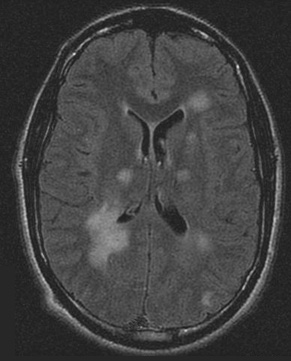

Séries de imagens de ressonância nuclear magnética (RNM) do cérebro de um paciente com encefalomielite disseminada aguda: lesões assimétricas "felpudas" sobre os cornos ventriculares bilaterais e tálamos

Do acervo pessoal de Catalina C. Ionita, MD; usado com permissão